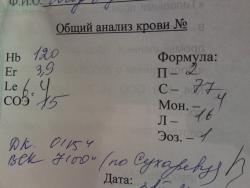

А вот в ОАК динамика есть (на фоне дезинтоксикации видимо)

От 2.03.11

И от 03.03.11